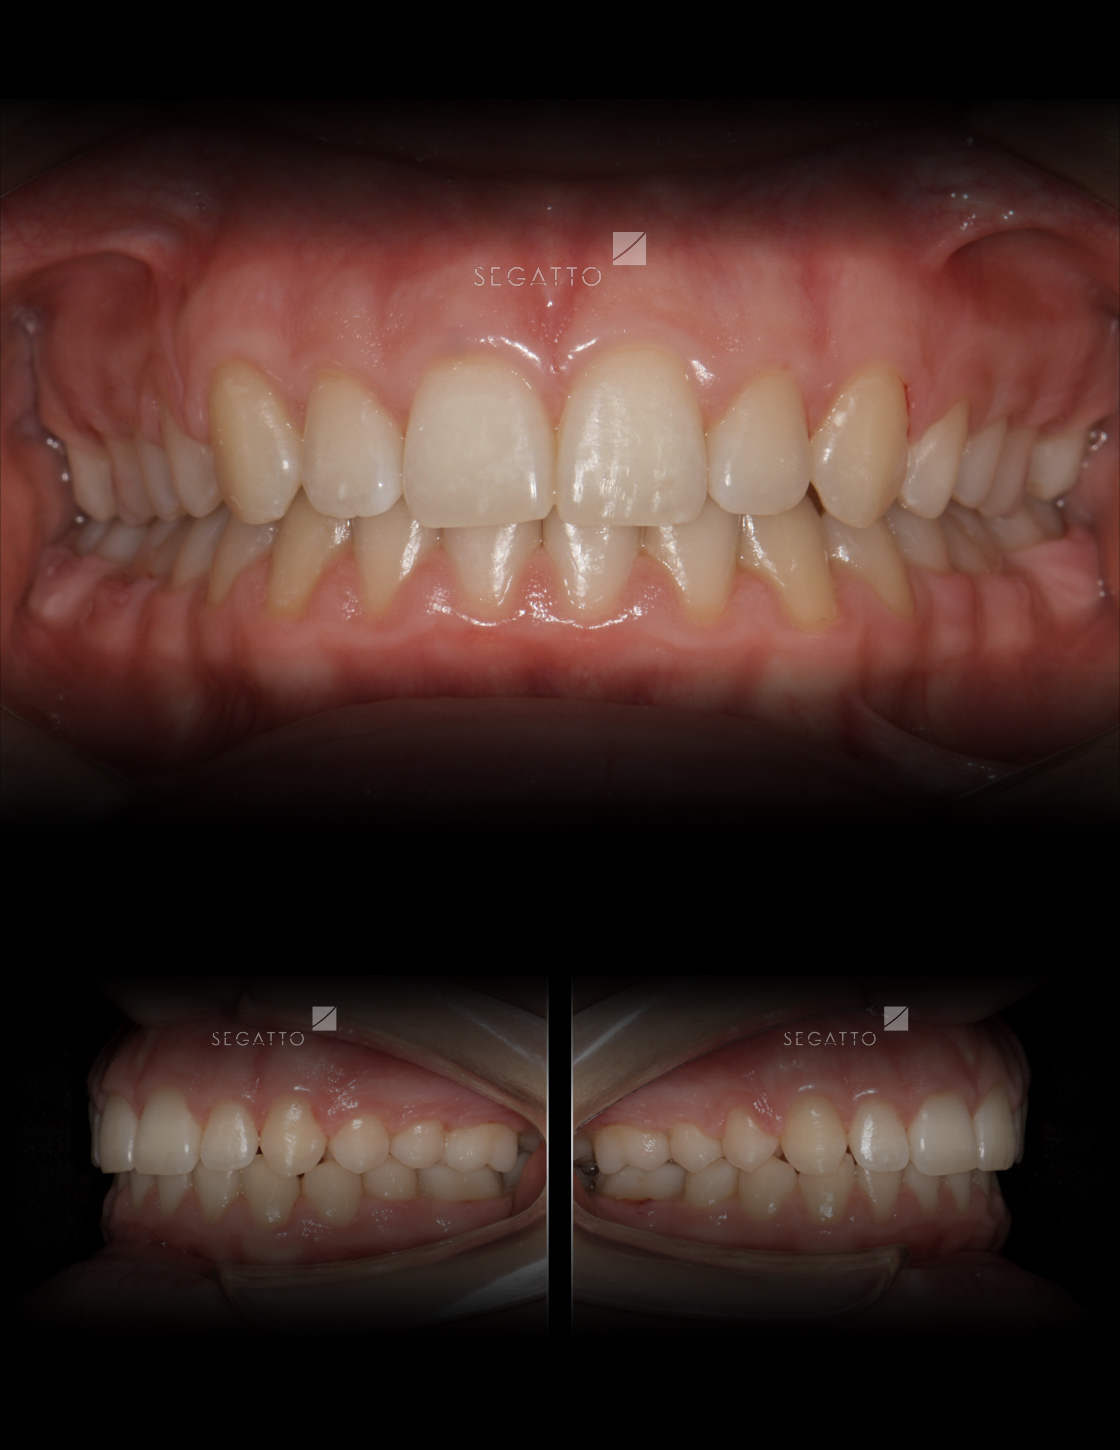

Orthodontics

Cases